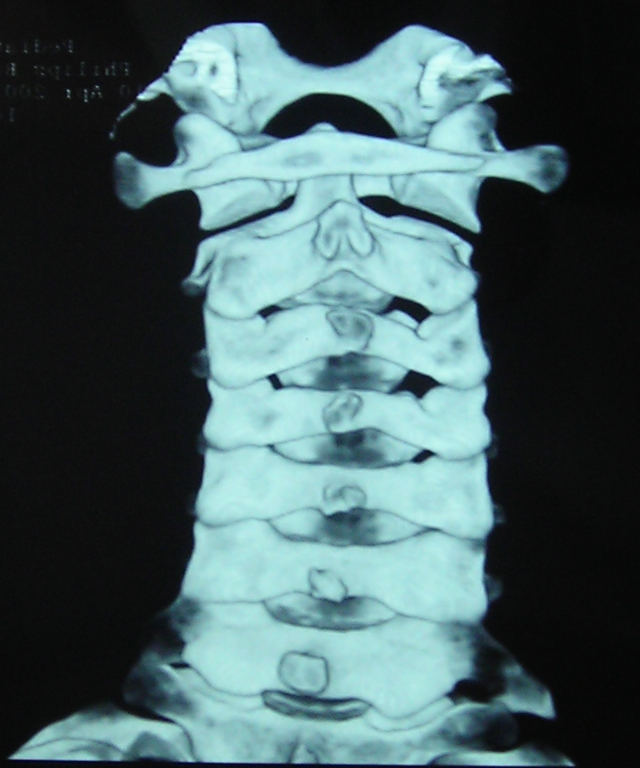

Аномалии тропизма шейного отдела позвоночника у детей. Клинические наблюдения, связанные с особенностью строения сегмента CII – CIII в литературе мы не обнаружили. Из группы пациентов проходивших с рабочими диагнозами острая кривошея были выделены четверо с особенностями клиники, заключающейся в невозможности сгибательно-разгибательных движений и выдвинутом вперед положении головы и небольшой кривошеей. На боковых рентгенограммах у них отмечалось распрямление шейного лордоза и перекрытие суставной щели дугоотросчатых суставов CII-CIII верхним суставным отростком СIII. У 2-х пациентов мы произвели 3-D КТ на которых обнаружили картины унилатерального подвывиха CII и различные плоскости расположения суставных фасеток СII-CIII справа и слева (рис.6).

Рис. 6 3-D КТ реконструкция шейного отдела позвоночника. Правосторонний унилатеральный подвывих CII. Хорошо визуализируется положение суставной поверхности справа на 300 по отношению к горизонтальной оси. Положение левого сустава практически горизонтальное.